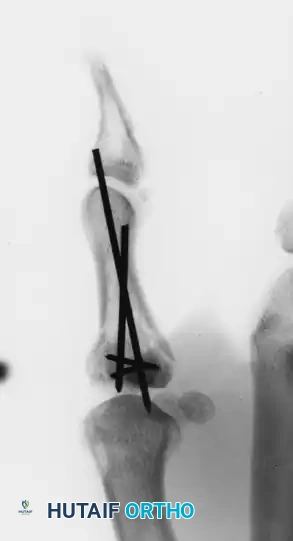

FIGURE 67-19 A and B: Preoperative anteroposterior and lateral radiographs demonstrating a highly comminuted, displaced intra-articular fracture of the base of the thumb proximal phalanx in a young male patient.

FIGURE 67-19 E and F: Postoperative radiographs confirming anatomical fracture fixation with simple, crossed Kirschner wires.